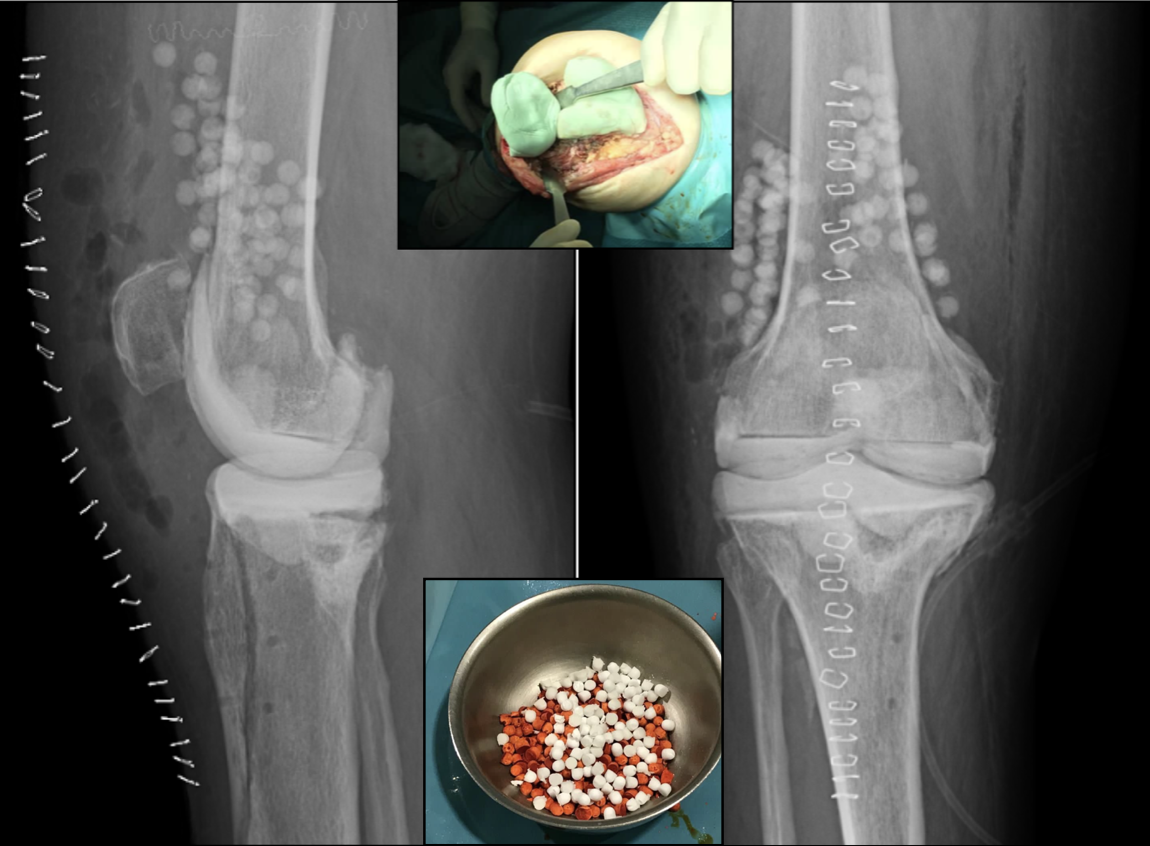

In all cases, 3 pre-filled cement packs with 1g gentamicin and 1g clindamycin (Copal G+C, Heraeus Medical GmbH, Wehrheim, Germany) were used, two for the femoral shield and one for the tibial plate, to which 2g streptomycin powder + 2g vancomycin were added for each cement pack used. Once the articulating spacer was implanted, after checking adequate stability and range of motion, 30 cc of calcium sulphate beads (STIMULAN® - Biocomposites® - Keele, UK) pre-loaded with antibiotic were added, following the usual surgical technique. 9 Two 10cc packets containing 400mg rifampicin powder and 300mg liquid isoniazid and one 10cc packet containing 2g streptomycin were used. The beads were inserted around both the femur and tibia, avoiding placement between the two components of the spacer. Finally, a plane closure was performed, paying special attention to the tightness of the arthrotomy closure in order to minimize the risk of prolonged drainage, previously observed with the intra-articular use of calcium sulphate [13]. (Figure 1) (Figure 2).

Figure 1

Figure 2

Figure 1: Calcium sulphate beads, already mixed with rifampicin (orange) and isoniazid (white).

Figure 2: Copal C+G® articulated spacer, with added vancomycin and streptomycin.